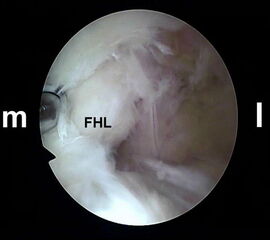

Es wird zunächst ein Weichteildebridement durchgeführt, bis die Flexor hallucis longus-Sehne identifiziert werden kann. Während des Debridements sollte auf die korrekte Ausrichtung der Instrumentenöffnung nach lateral geachtet werden. Im Verlauf empfiehlt sich der Wechsel auf eine bipolare Ablationselektrode, die eine gezielte Freilegung der Strukturen unter gleichzeitiger Blutstillung ermöglicht, ohne dabei unkontrolliert Gewebe anzusaugen (rechte Seite, m=medial, l=lateral). Das Os trigonum bzw. die Osteophyten sowie die FHL-Sehne müssen vollständig dargestellt werden (*=Os trigonum, FHL=Flexor hallucis longus-Sehne).